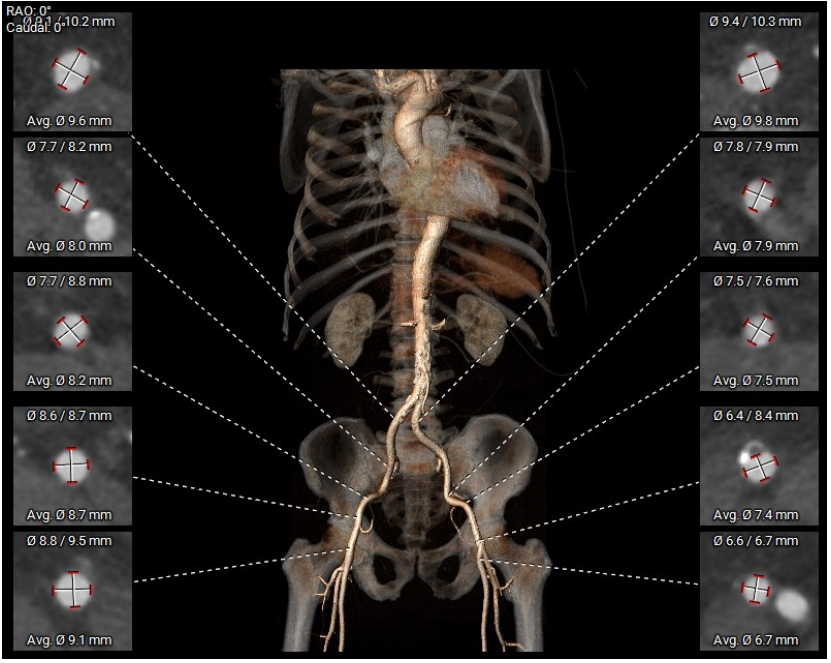

三叶瓣,瓣环偏大,右无瓣叶钙化重;LVOT直径小于瓣环直径,呈漏斗形;窦部直径可,STJ及升主直径偏小,双冠脉高度可;主动脉根部角度约39°;室间隔及室壁增厚,LV偏小。

环上钙化分布较为均匀,限制区高度4-12mm,开口最受限处位于环上8mm,预估瓣膜锚定良好。

双侧股动脉入路内径可,走行良好,主动脉弓部及腹主动脉可见钙化。

三叶瓣,瓣叶钙化重,限制区高锚定力可,LVOT上宽下窄有利于密封,预装29型号Evolut PRO瓣膜;